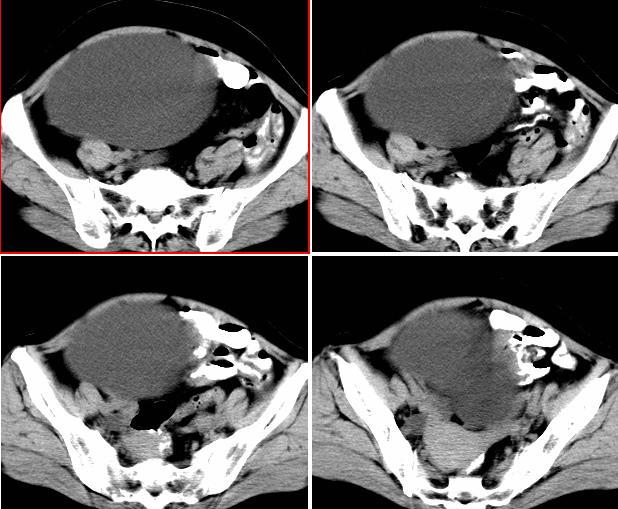

女,52岁,外伤后一小时入院,腹部b超示盆腹腔巨大无回声包块,右肾大小约208*107mm,追问病史,腹部逐渐隆8年余,无明显体重下降、消瘦、黑便呕血史,无大便性状改变,2年前已停月经,有高血压病史8年余,pe:血压180/100mmhg,全身皮肤粘膜无黄染、苍白,全身浅表淋巴结无肿大,腹部膨隆,呈蛙腹,可触及腹部有一14*15cm大小包块,质软,边界清楚,移动度可,无压痛,叩诊呈浊音。辅助检查:肝功能白蛋白43g/l球蛋白35.2g/l余指标正常,血糖电解质凝血四项正常。血常规hb115g/l白细胞13*10/9/l n0.85肾功能bun6.53mmol/l cr124umol/l.

右侧后腹膜巨大囊性肿块影阴,边缘清晰,内见膜状分隔,均匀水样密度,右肾影阴消失,囊块所到区域脏器受挤移位,右侧输尿管扩张,应该考虑:右肾重读积水,巨大肾囊肿不除外。引发肾性高血压。

腹部巨大囊性占位,膨胀性生长,边界光整,囊内容物为水样密度,其内可见多发分隔,纵观所有层面,正常右肾未见,考虑为来源于右肾的巨大多房性肾囊肿(多房性囊性肾瘤)可能性大。

该病来源和病因不明,儿童为先天性,多在5岁以下发病,成人多见于40-70岁女性,ct表现:单房或多房囊性病灶,有厚的囊壁,大部分有分隔,部分可出现环形、沙粒状钙化。

腹部巨大囊性占位,膨胀性生长,边界光整,囊内容物为水样密度,其内可见多发分隔,右恻输尿管全程扩张,纵观所有层面,正常右肾未见,考虑为来源于右肾的巨大多房性肾囊肿可能性大。

反推一下:1.那么重的积水,引起积水的原因大部分是右侧输尿管有梗阻,排出受阻。右侧输尿管应该也是重度扩张才对。2.如果是肾积水,而且是右侧输尿管问题引起,那么病人肯定有相应的临床症状:比如输尿管结石引起的血尿、剧痛等症状,至少也会急性发作病史。另,本例显然不需要考虑输尿管癌,膀胱也挺好,更没有无痛性血尿病史。病人8年多没有其他的不舒服,只是腹部日渐膨隆,临床症状显然不支持。3.如果是重度肾积水的话,应该可以看到被压缩的肾皮质,即使很菲薄也多少会有显示的。

右肾明显扩大,皮质菲薄,间隔细,右输尿管全程扩张,右肾重度积水,原因应重点查输尿管膀胱接合处。